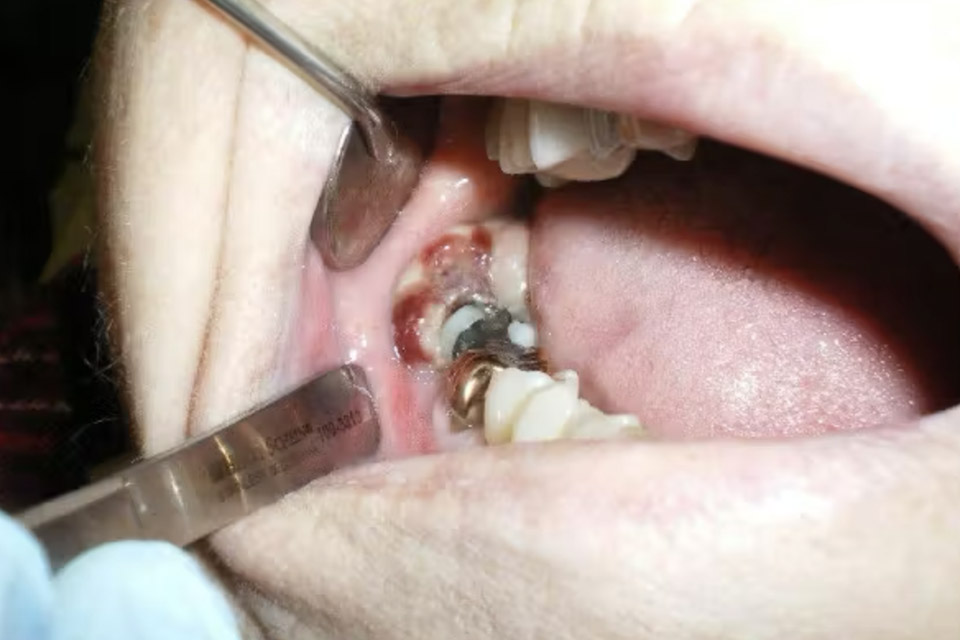

Khối tròn đường kính 2,5 cm, màu hồng xám, vị trí phía sau răng số 31.

-

Mô u dễ chảy máu, không đau khi ấn.

Răng số 31 lung lay độ II, đau nhẹ khi gõ.